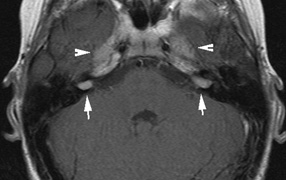

Intracranial leptomeningeal capillary vascular malformation (Figs. 21 and 22) is associated with seizures and contralateral neuromuscular weakness. Central nervous system involvement correlates highly with ipsilateral involvement of the V1 dermatome by a PWS.208,218

Fig. 22. Axial T2-weighted (a) and coronal T1-weighted (b) images of a 16-year-old boy with a port-wine lesion over the right side of his face. The right hemisphere is markedly atrophic and abnormal draining veins are seen within the right lateral ventricle (arrowheads). (c, d) The entire right hemisphere is covered by an enhancing pial angioma and the choroid plexi are enlarged. Enhancing retinal angiomas (arrows), typical of Sturge-Weber syndrome, are seen in (d).